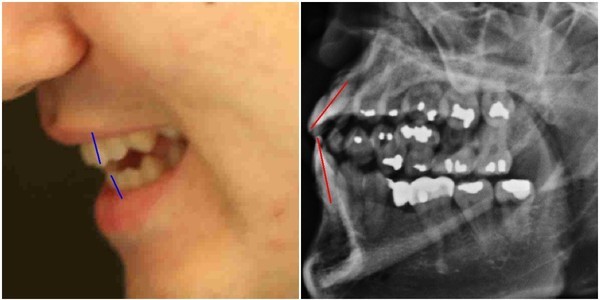

- ▲ 박주신씨 명의의 치아엑스레이와 실물사진 비교. ⓒ 뉴데일리DB

나아가 피고인들은 주신씨 명의의 치아엑스레이 및 진료기록을 바탕으로 ①만 20세의 나이에 이미 썩어 옆으로 기울어진 사랑니의 상태, ②미국 치과교재에서도 사용을 금기시하고 있는 캔틸레버브릿지 시술을 한 사실, ③저작(咀嚼) 기능에 매우 중요한 역할을 하는 아래쪽 어금니 2개가 빠진 상태에서 수년간 방치된 사실 등을 의혹의 근거로 들고 있다.

앞서 지난 공판에서 유명 치대에 재직하고 있는 A교수는, 주신씨 명의의 치아엑스레이 및 주신씨의 실체 치아상태를 볼 수 있는 실물사진과의 비교를 통해, 엑스레이 속 피사체를 주신씨로 볼 수 없다는 의견서를 재판부에 제출했다.